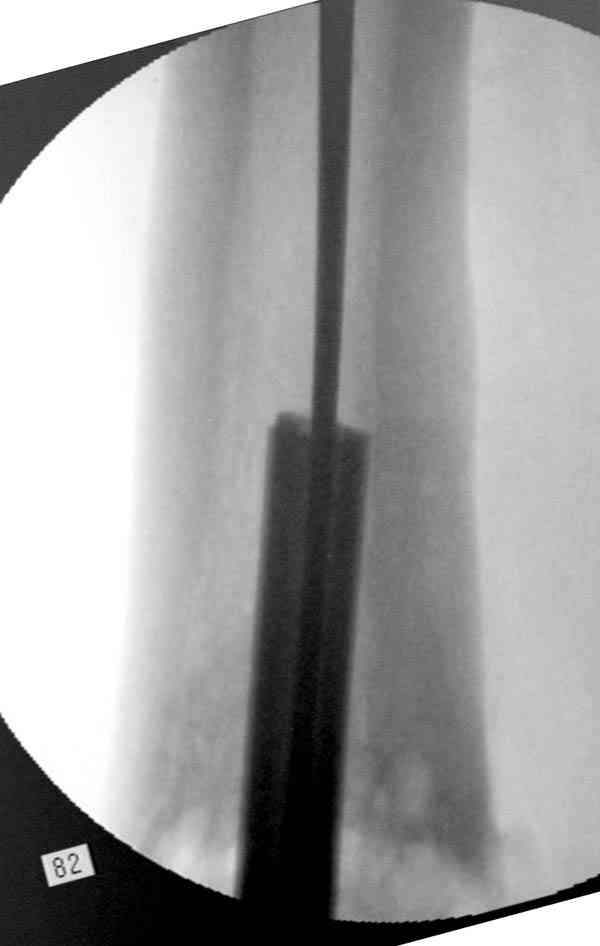

Приспособление для удаления сломанных штифтов и наличие ЭОП облегчит

задачу. При отсутствии крючка тогда можно применить обычный длинный

ball pointed guide wire от интрамедулярного набора. Проволока,

пропущенная за пределы гвоздя и зажатая другая вытащат сломанный

конец штифта без проблем.